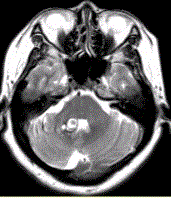

问题 患者女,41岁。头痛半年,加重10d。头部MRI显示如下图。 根据该病的影像学表现,该病可能的诊断是

选项 A.海绵状血管瘤 B.发育性静脉畸形 C.AVM D.毛细血管扩张症 E.动脉瘤 F.硬脑膜动静脉瘘

答案 AB